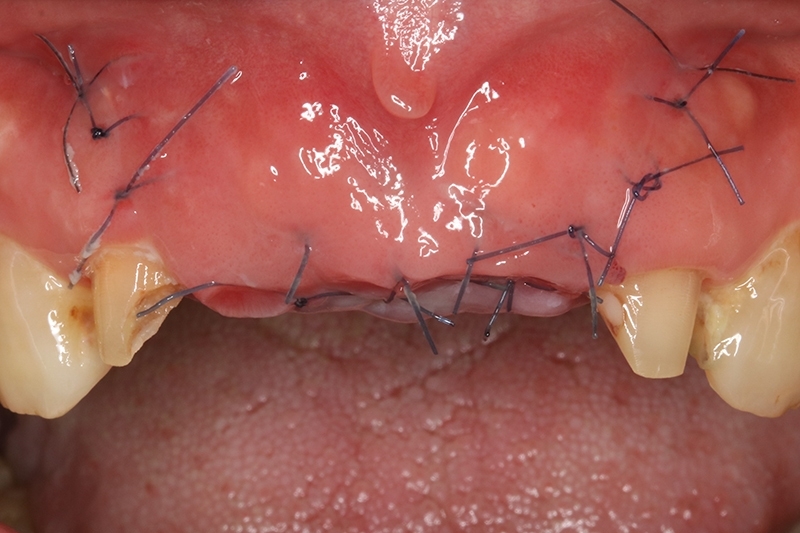

初步等待2個月軟組織癒合,再來進行垂直脊水平骨牙脊增寬術,使用不可吸收再生膜Cytoplast 及迷你骨釘 Tack固定放置的人工骨粉。

明顯看到水平骨頭缺損範圍

垂直骨頭缺損情況

不可吸收再生膜Cytoplast

修剪合適範圍,並在舌側固定

迷你骨釘Tack固定再生膜及骨粉

迷你骨釘固定再生膜及骨粉